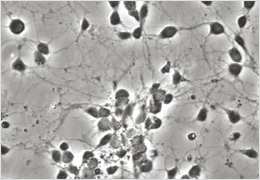

【研究分野】 生命機能工学

・ 脳神経系の疾患進行の分子機構の解明とそれら疾患の治療戦略の確立

・ ビズフェノールAによる脳内神経細胞への影響評価

・ エピジェネティック制御による神経細胞への分化機構の解明

神経細胞の顕微鏡画像